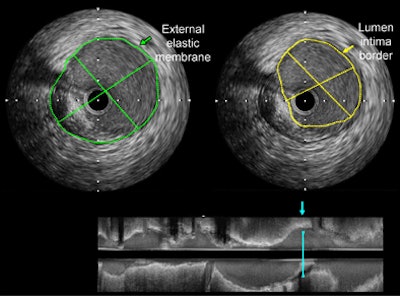

| Images show quantification of proximal left anterior descending artery plaque in a 71-year-old male nonsmoker with hypercholesterolemia. Top: Cross-sectional intravascular US view with traced external elastic membrane (green arrow) and lumen-intima border (yellow arrow). Bottom: Longitudinal intravascular US view of the plaque. Blue arrow = position of cross-sectional views. Images republished with permission of the Radiological Society of North America from Radiology, September 9, 2010, online before print, doi: 10.1148/radiol.10100681. |